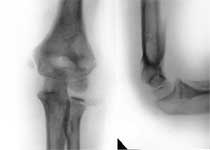

1.Перелом плечевой кости.

2.Остеосинтез с помощью аппарата Веклича.

3.Результат лечения.